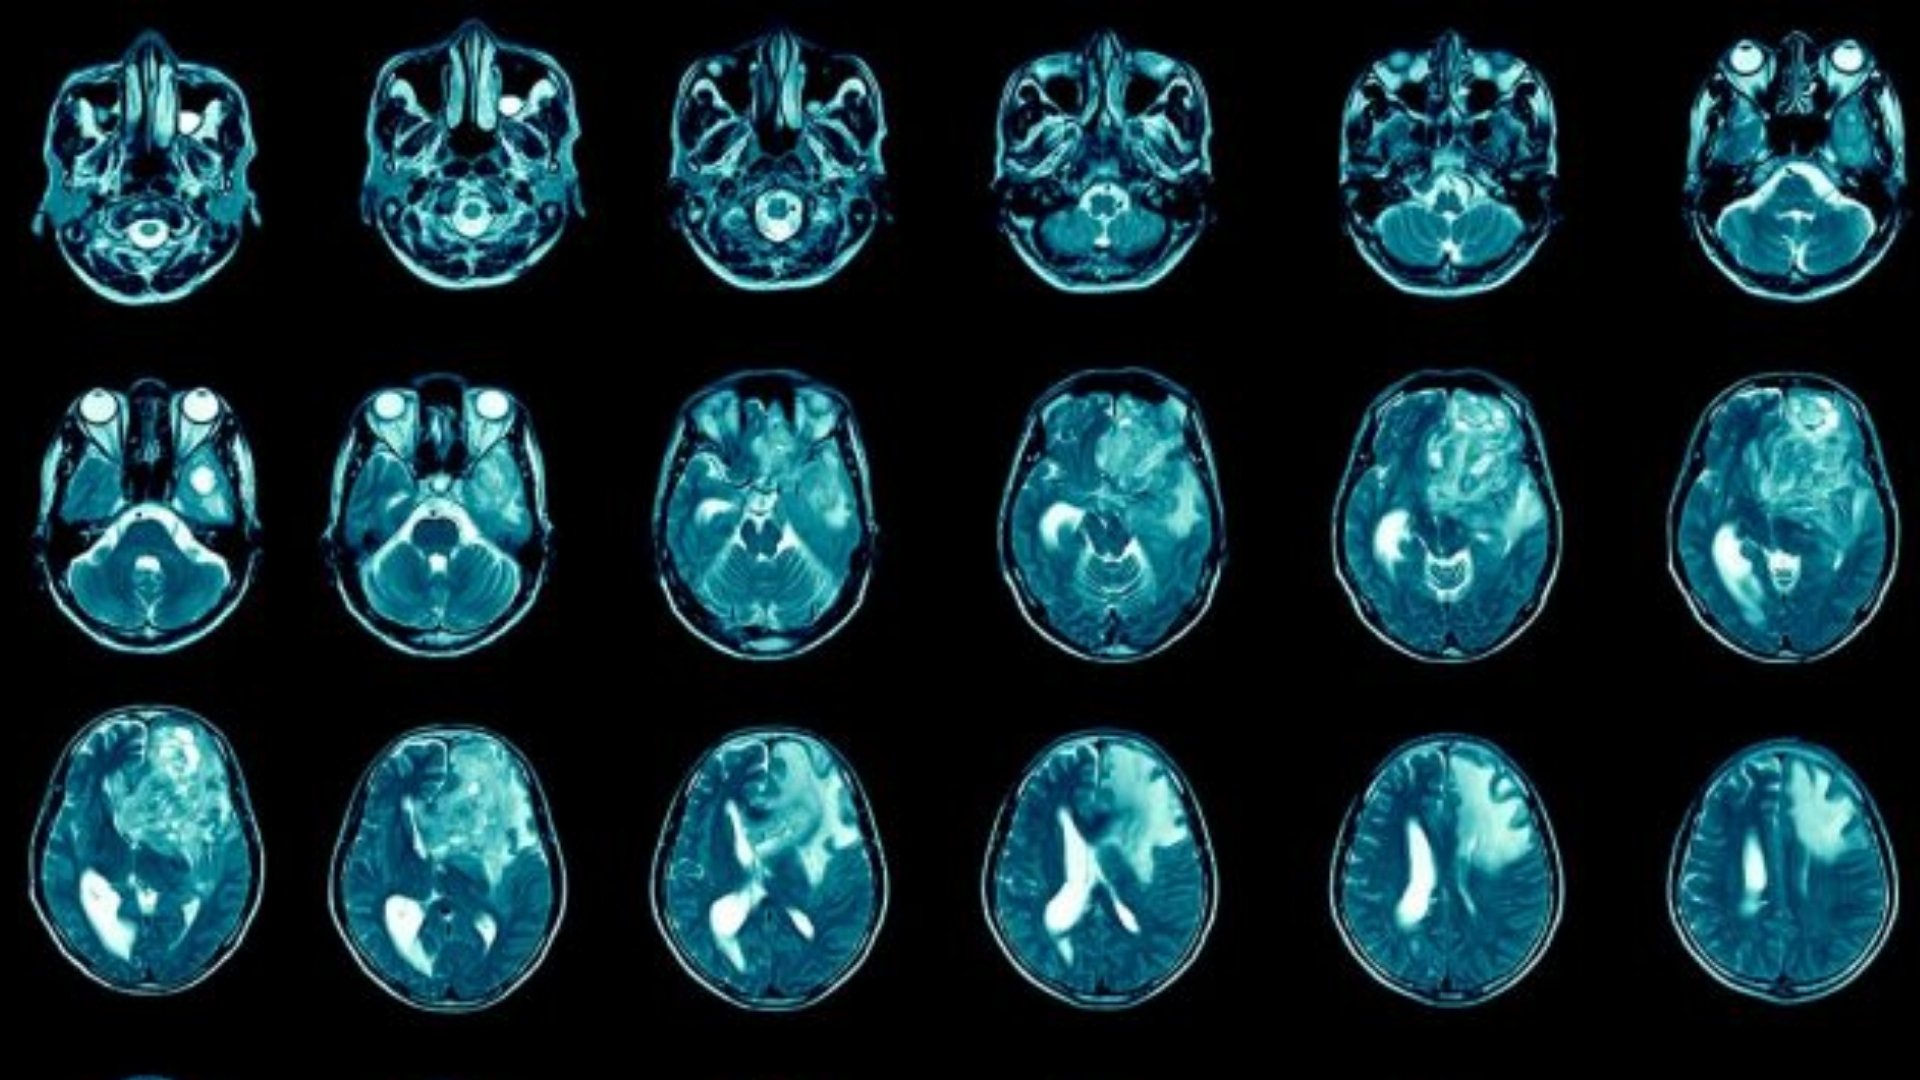

什麼是膠質母細胞瘤 (GBM)?

膠質母細胞瘤 (GBM) 是最具侵襲性的原發性腦癌,起源於膠質細胞 - 神經元周圍的支持性組織。Glioblastoma (GBM) 腫瘤的特徵是細胞快速增殖和顯著的新陳代謝變化,嚴重依賴葡萄糖新陳代謝。具體來說,GBM 腫瘤細胞呈現沃伯格效應 (Warburg effect),癌細胞的葡萄糖代謝率比正常細胞高出 200 倍,從根本上改變了細胞的能量平衡和增殖。

及早發現症狀可顯著改善膠質母細胞瘤 (GBM) 的預後和治療效果。膠質母細胞瘤 (GBM) 通常會出現腦內位置相關的症狀,通常是由於顱內壓增高和局部組織破壞所致。